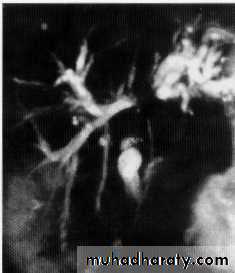

MRCP + ERCP